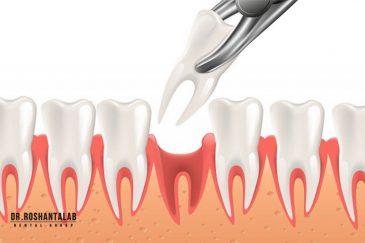

از عصب کشی و درمان ریشه دندان گرفته تا جراحی لثه و کشیدن دندان، تمامی مراحل توسط متخصص ترمیم دندان مدیریت میشود. ارائه باکیفیتترین خدمات ترمیم دندان برای سلامتی شماست.کاشت ایمپلنت فوری دندان